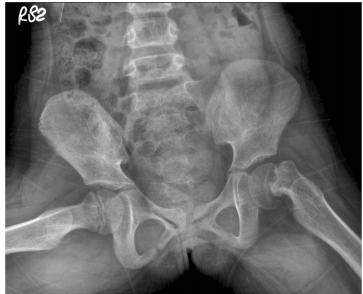

74.15歲男生因鼠蹊部疼痛跛行而求診,其青蛙姿勢X光如圖示,則最可能診斷為何? (A)肌肉拉傷 (B)股骨頭近端生長板滑脫症 (C)腹股溝疝氣 (D)外陰部挫傷